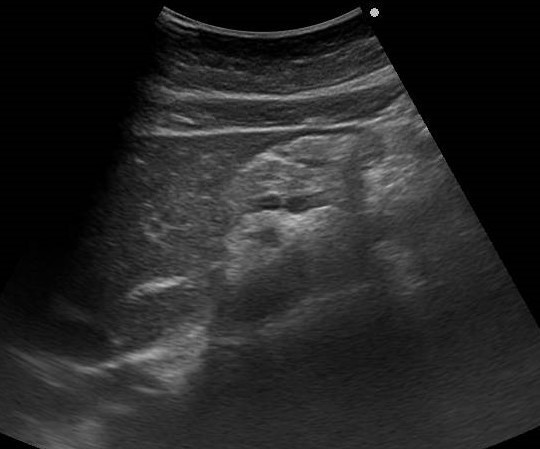

さらに、肝臓・膵臓・胆のうといった上腹部臓器に限らず、腎臓や膀胱も胃も大腸も虫垂なども症状や病状の経過によっては評価していきます。腸管内にガスが多くて見えずらいことや、内臓脂肪が多く評価しがたいこともありますが、それも一つの所見としてとらえ、症状の原因検索に大いに役立ちます。

患者さんの中には、「少し前から胃が痛くて・・・」という症状で来院される方がいます。胃のあたりをさすって症状を伺いますが、おなかには胃だけではなく多くの臓器が複雑に存在し機能しています。胃潰瘍やポリープの診断は内視鏡が得意な分野ですが、消化管の外を見ることができる超音波と組み合わせることで、格段に症状に関連した情報が増えます。